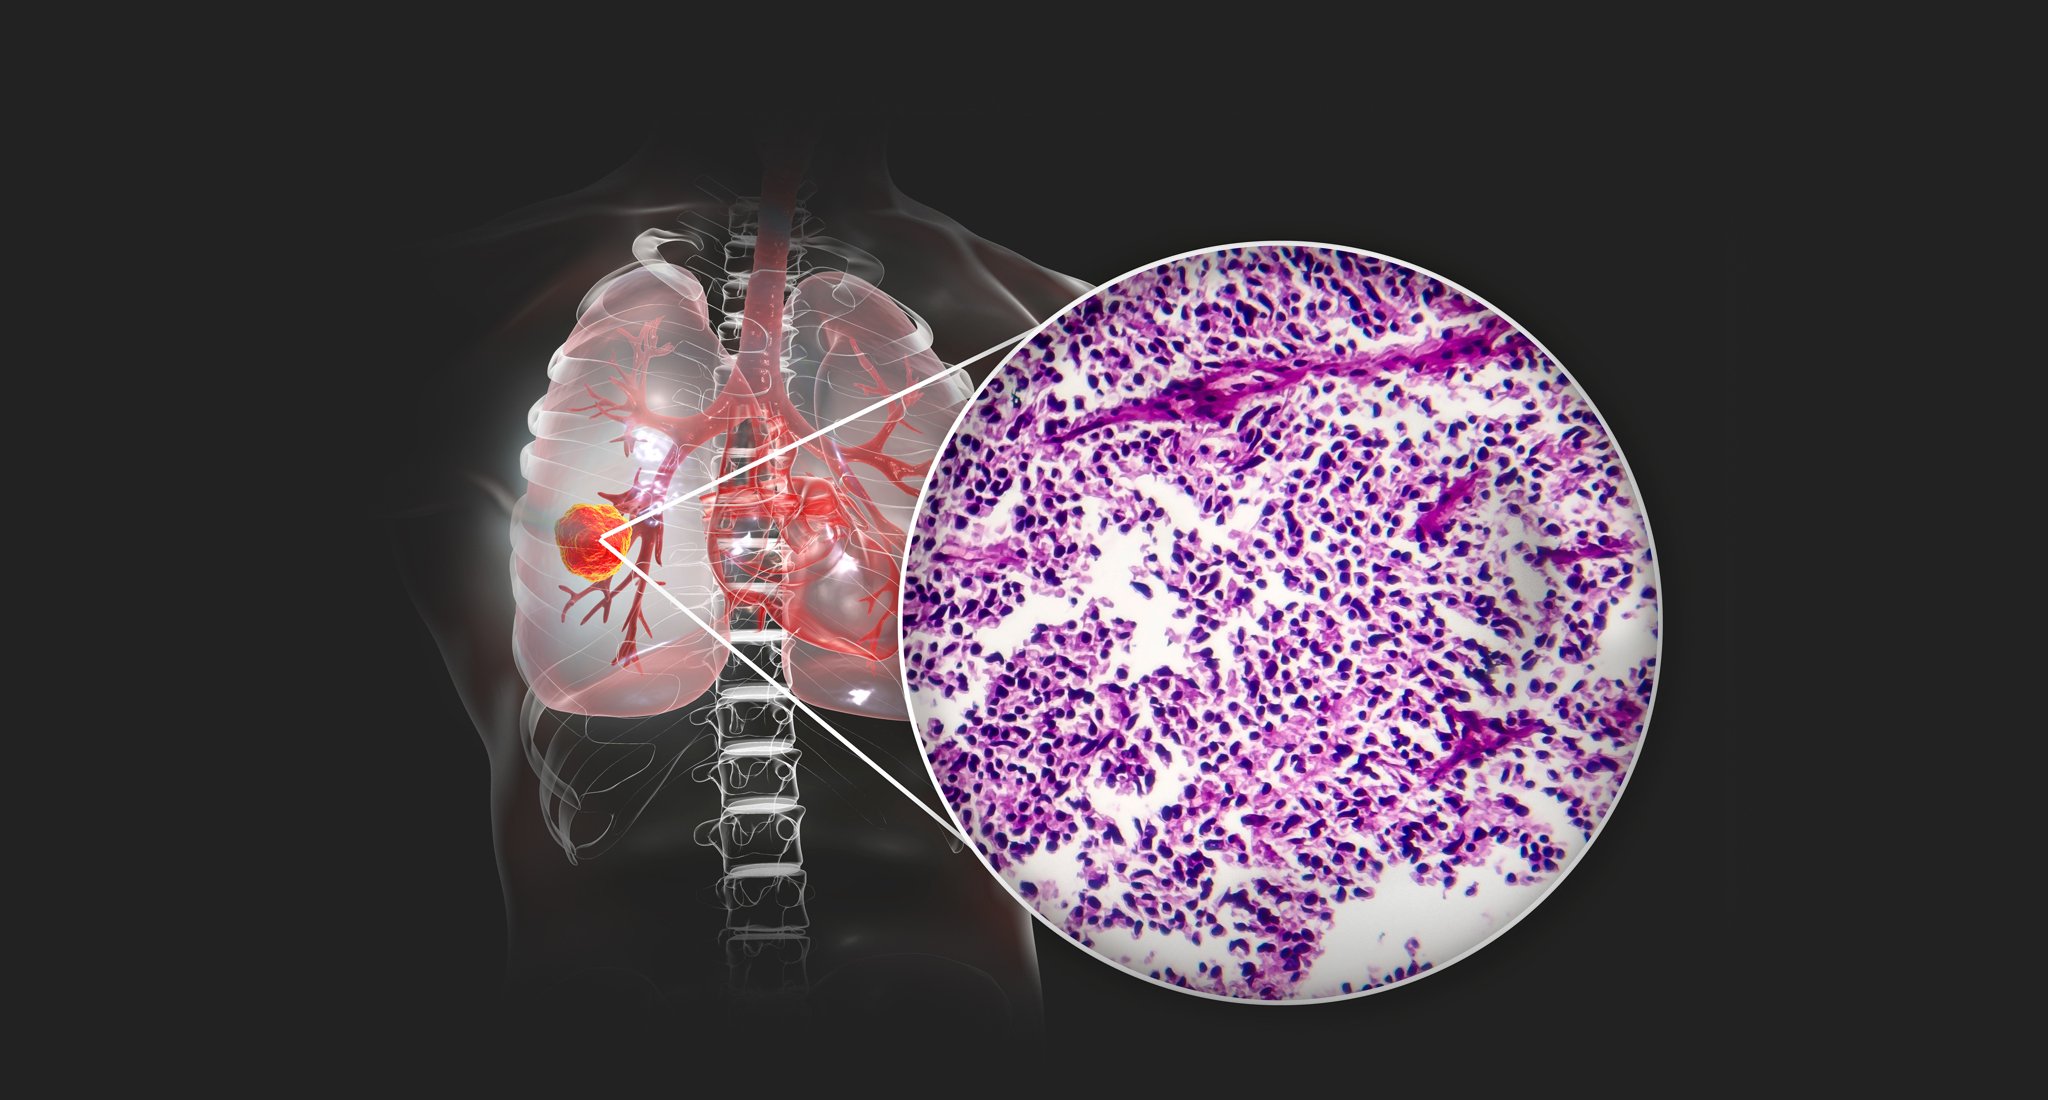

FDA has recently approved Sotorasib to treat KRAS G12C-mutated non-small cell lung cancer. This newly invented targeted therapy is a boon for the patients with KRAS mutated non-small cell lung cancer (NSCLC), who have achieved a poor prognosis following first-line treatment and are left with limited treatment choices.

KRAS is one of the frequently found mutated genes in patients with NSCLC. It is detected in approximately 30% of lung adenocarcinomas and is a target for researchers. It was known to be the first oncogene (a mutated form of a normal gene that causes cancers) ever diagnosed (1983). For the past 40 years, this elusive kind of KRAS has scuppered the drug developers.

Recently, a breakthrough success has been achieved in the field of knocking the KRAS gene down. The largest clinical trial has been operated to date for determining the outcomes of Sotorasib, particularly for patients with KRAS G12C mutation. The trial involved 124 patients with KRAS 12C mutated metastatic or locally advanced NSCLC, who showed disease progression following chemotherapy or immunotherapy.